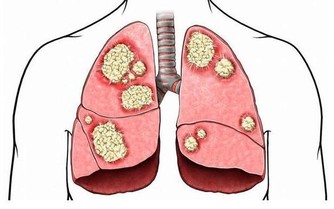

5、心肺功能不佳,改善呼吸道感染,穩定心律。